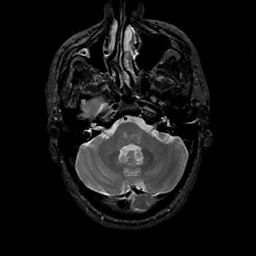

MR Study #11, May 5, 1991 -- Slice #11